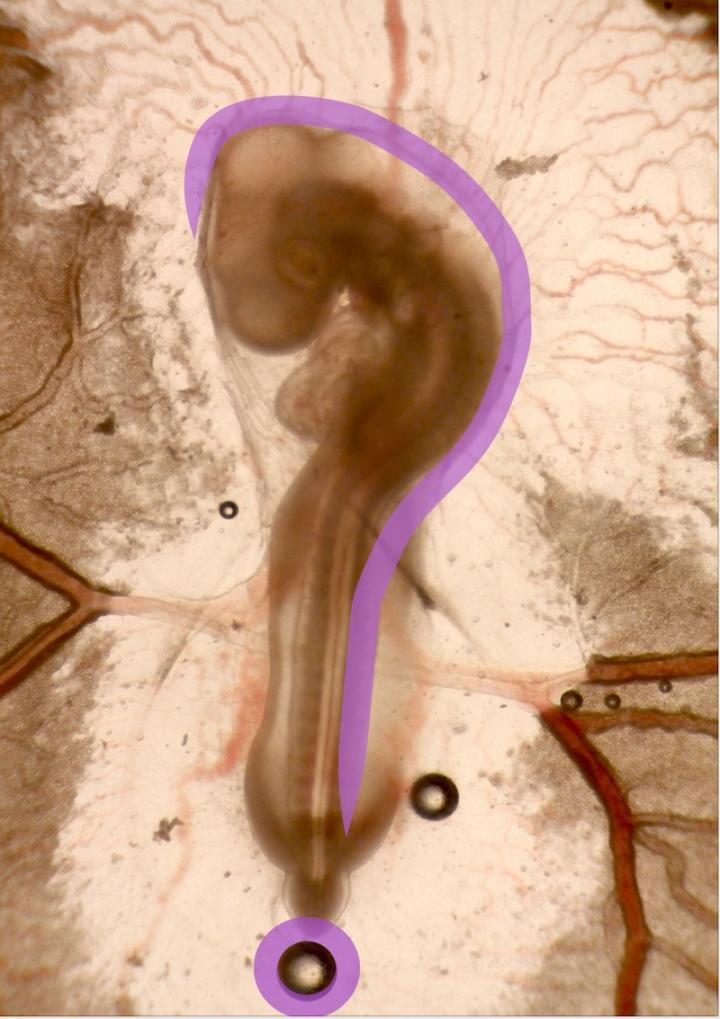

Chen's proposal was one of just three selected from institutions across the country as part of the NSF/CASIS solicitation to further knowledge of tissue engineering and mechanobiology utilizing the ISS. With the funding for his project, " ISS: Unveiling the Mechanical Roles of Gravity and Buoyancy in Embryonic Brain and Heart Torsion, " he aims to identify the biomechanical mechanisms that drive the shape changes in early embryonic brain and heart development.

Building on his previous studies, Chen, who will serve as principal investigator, will test the effects of buoyancy and gravity on the growth and shape of brains and hearts in chicks' early embryonic development, which closely parallels that of humans. The data should lead to a better understanding of birth defects found in humans such as situs inversus, in which organs are found in the mirror image position in the body, which leads to difficulty in finding replacement organs, should they be necessary.

The researchers also hope to better understand left-right asymmetry of the body, as well as how the brain develops its shape under normal and micro-gravity conditions. Both studies could prove useful for future deep space travels.